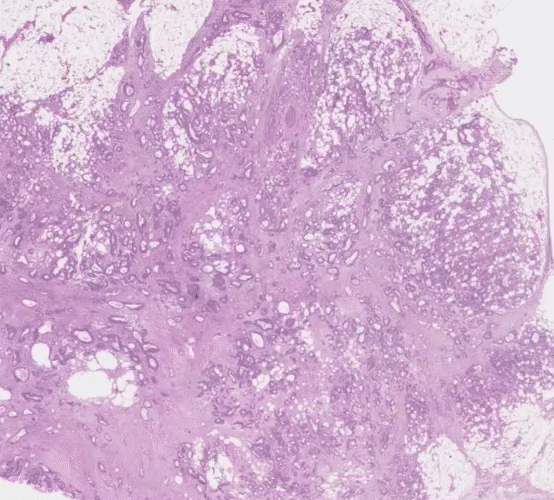

One cluster of patches in particular stood out as a visually-distinct feature involving high grade tumor (i.e., least-resembling normal colon tissue) in close proximity to adipose (fat) tissue, which we dubbed the “tumor-adipose feature” (TAF). This feature was strongly associated with high-risk AI predictions and also strongly predictive of poor prognosis when considered as an independent feature. We also found that it could be accurately identified by both pathologists and non-pathologist researchers. While further work will be required to better understand the biological significance of “TAF” and to validate the ability of pathologists to consistently identify this feature in routine pathology slides, this finding represents the discovery of a human-interpretable feature in pathology using an AI-based approach. Moving forward, we and others continue to work on AI applications such as those described here as well as new imaging approaches to further elucidate disease processes in histopathology. The results of these efforts may offer the promising potential to inform clinical decision making, discover novel biomarkers, and improve tissue processing and diagnostic workflows in pathology.

Left: H&E pathology slide with heatmap indicating locations of the independently prognostic Tumor Adipose Feature (TAF). Regions highlighted in red/orange are more likely to represent TAF according to the image similarity model, as compared to regions highlighted in green/blue or regions not highlighted at all. Right: representative collection of TAF patches across multiple cases. Pathologists and researchers who first reviewed a set of example patches such as these could reliably identify new examples of TAF patches.